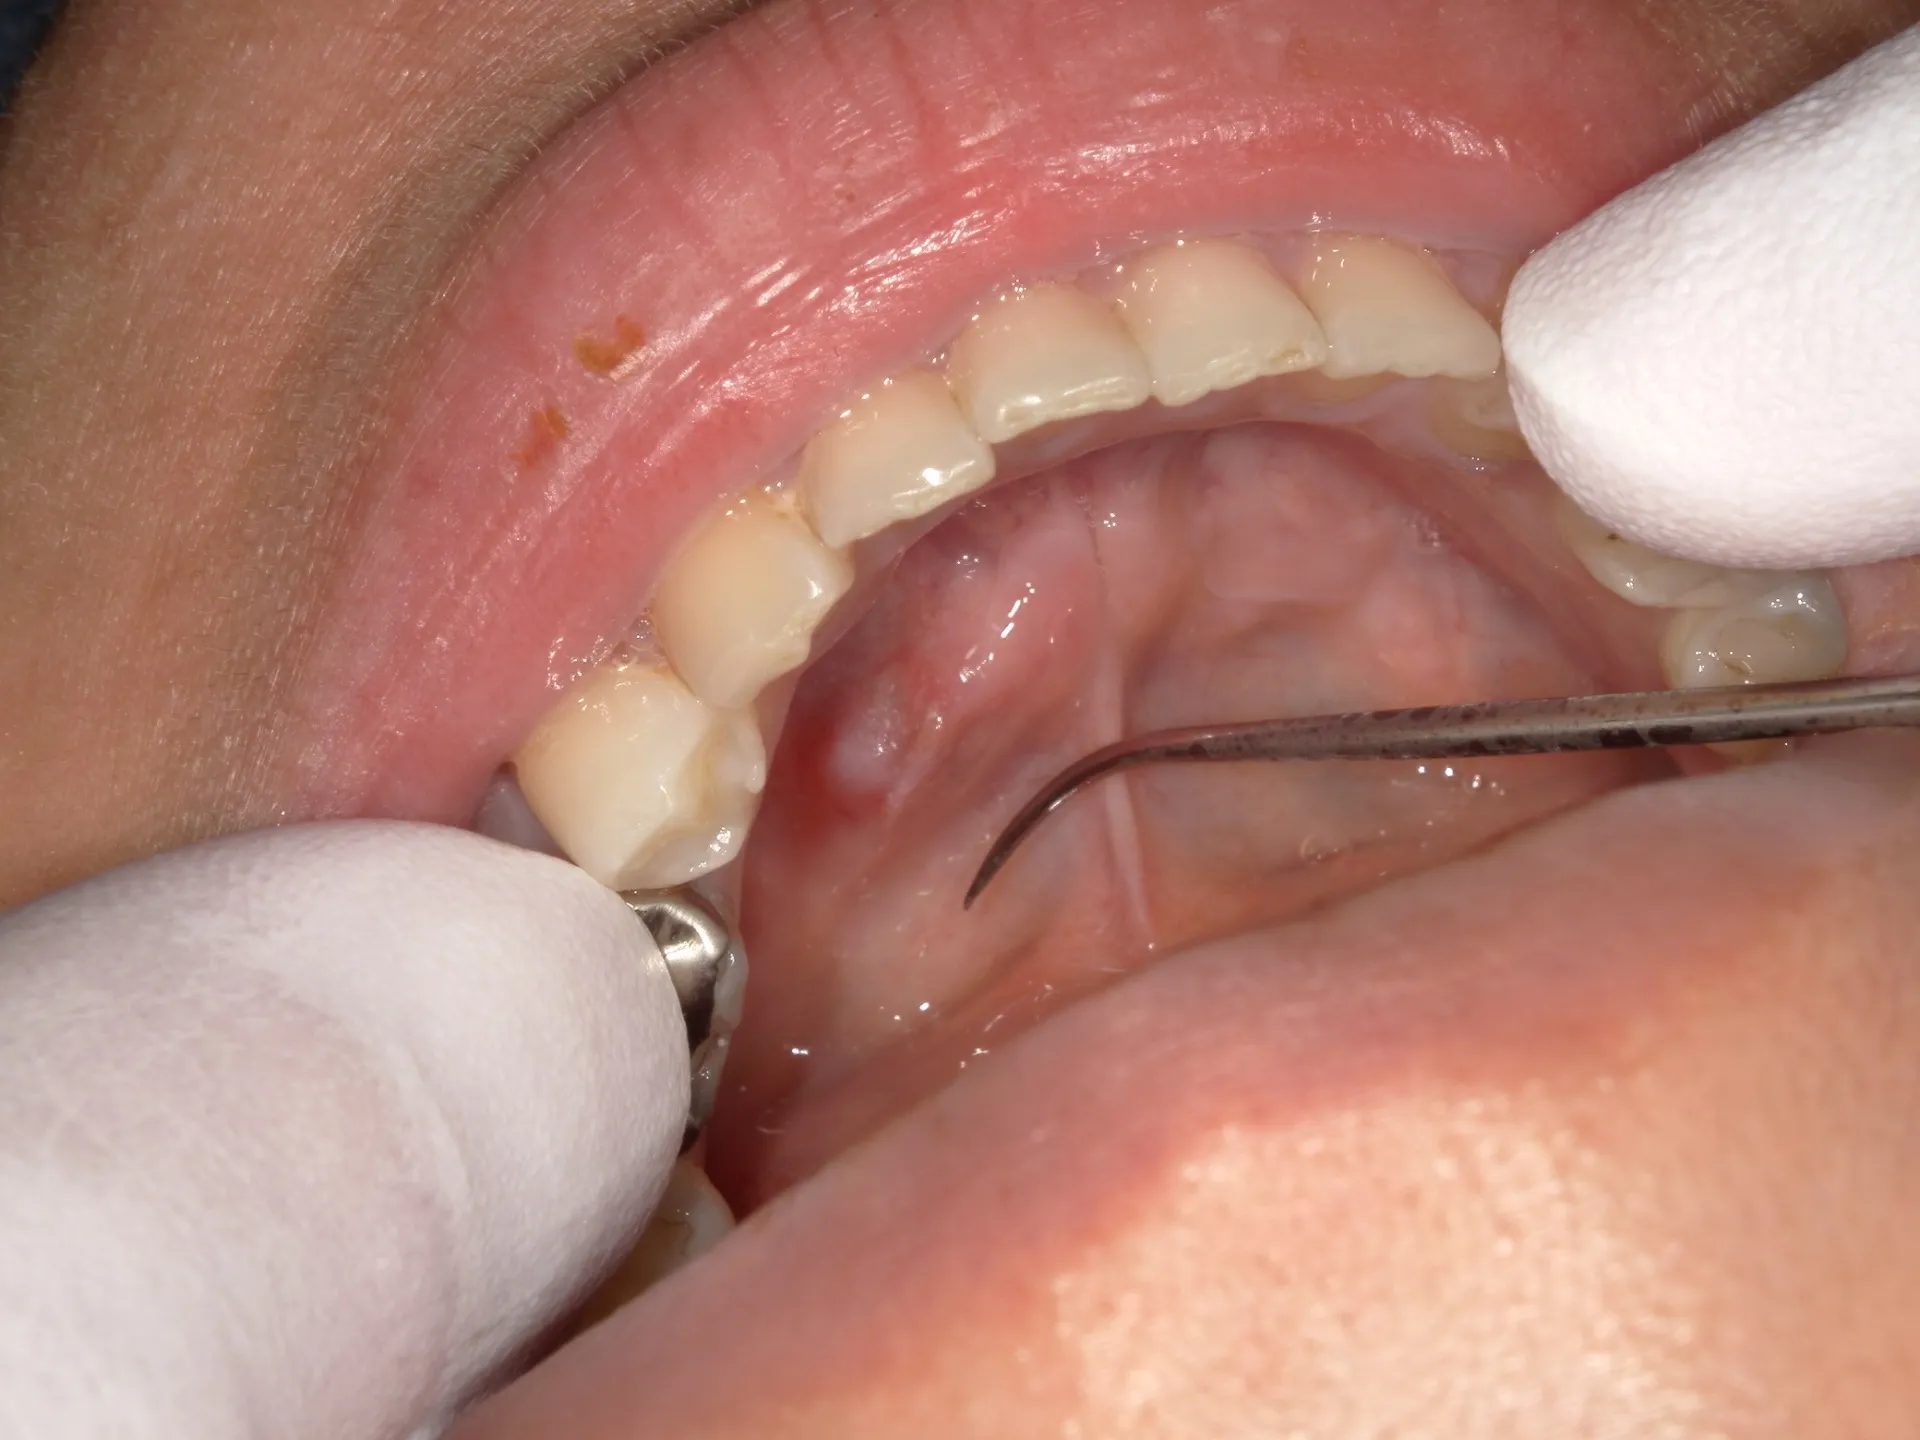

舌の下が腫れる「ガマ腫」とは? 2025/11/12 こんにちは!千葉県市川市の妙典駅前にある妙典歯科Nクリニックです。粘液嚢胞 「ガマ腫(がましゅ)」は口の中の唾液嚢胞(のうほう)の一種で、特に舌の下(舌下腺や小唾液腺の導管の損傷)によって生…